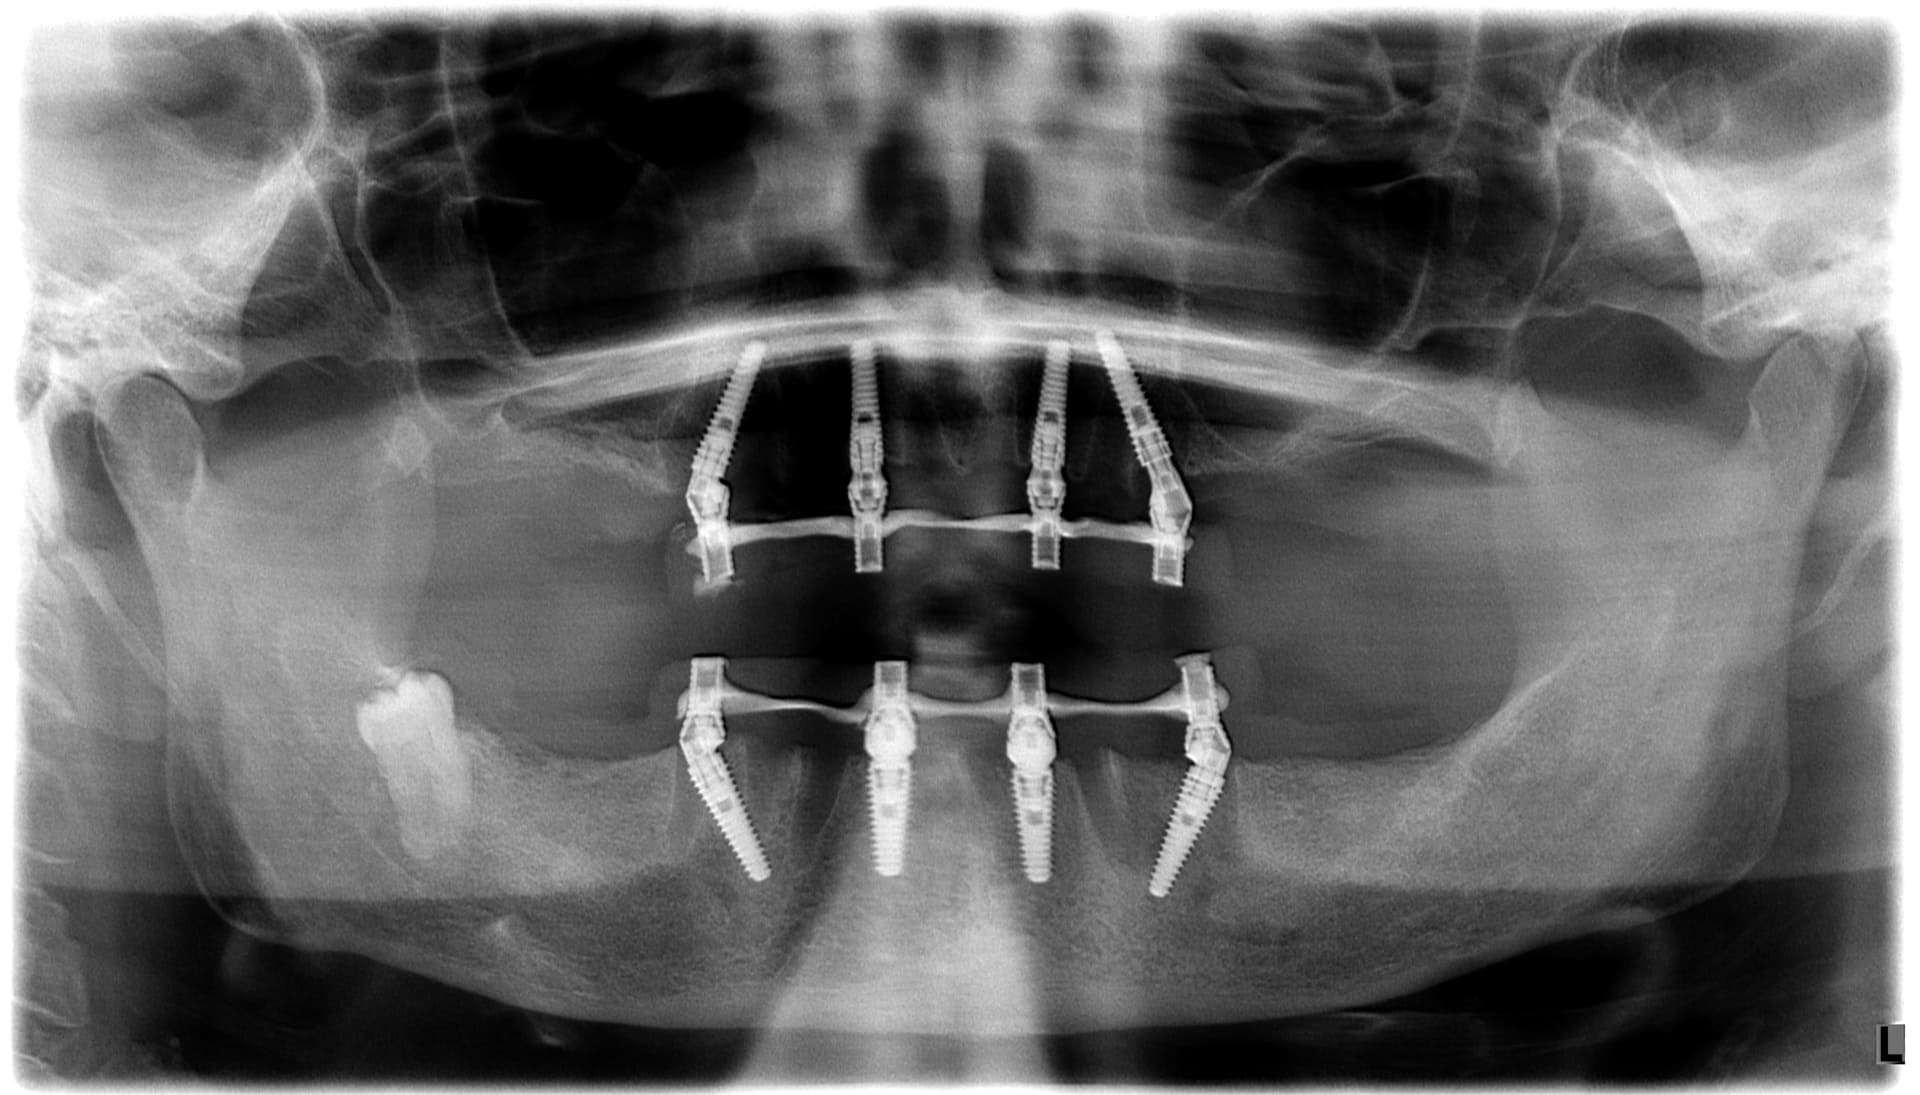

Casi clinici

Paziente 1

Dopo >